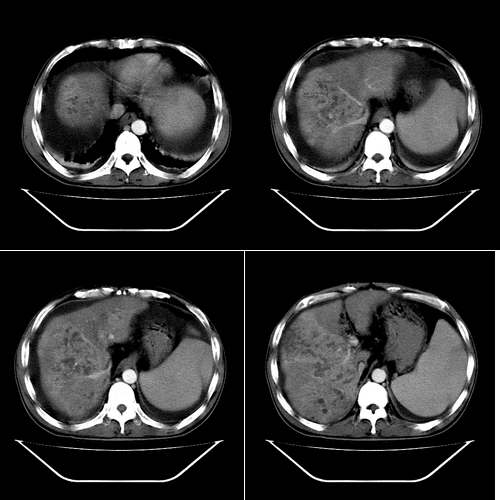

以下是引用yz在2006-6-2 12:20:00的发言:[br]肝左右叶比例失调,左叶体积明显缩小,肝边缘凹凸不平呈波浪状外观,肝左右叶可见不规则之斑片状低密度影,边界不清,以右叶为甚,肝门区增宽,增强后于动脉期病灶不均匀强化,门脉及延迟期均呈低密度,门脉主干及其右支无强化,以门脉右支明显,其内可见低密度影充填,门脉主干周围可见强化的细小侧支循环血管影。脾大,脾门血管明显增粗,脾后左侧膈脚前可见串珠状增粗强化血管影,并见胸腹水征。[br]1、考虑为弥漫性肝癌并肝门静脉主干及其右支癌栓形成,门脉海绵化。[br]2、肝硬化,脾大并门脉高压。[br]3、双侧少量胸水、腹水。